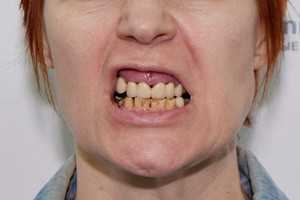

Вторая стадия пародонтита считается достаточно запущенной. Воспаление уже приобрело необратимую хроническую форму, все признаки заболевания становятся ярко выраженными. Характерными симптомами данной стадии считаются достаточно объемные десневые карманы, оголение зубов, ярко выраженный неприятный запах изо рта, патологическая подвижность. На рентгене хорошо прослеживает рецессия, то есть разрушение костной ткани – именно этот факт больше всего осложняет лечение.

Специфические признаки пародонтита средней степени тяжести

Симптомы данной стадии выражены достаточно ярко. С гингивитом такой пародонтит уже не спутать – присутствует оголение и подвижность зубов, десна становится гипертрофированной, чего при поверхностном воспалении не бывает. Патологический процесс уходит глубоко в комплекс тканей пародонта, помимо десен задействуются уже и связочный аппарат, и костная ткань.

Пациенты, кому поставлен диагноз «пародонтит II стадии», жалуются на болезненный прием пищи, психологический дискомфорт, поскольку внешний вид улыбки заметно искажается в худшую сторону, на социальные проблемы, ведь из-за неприятного и даже гнилостного запаха изо рта многие ограничивают контакты с другими людьми, отказываются от важных деловых или личных встреч.

Покраснение и отечность десен сохраняются, присутствует зуд, ярко выражена болезненность от механического воздействия (реакция на контакт с щеткой или едой, на горячее/холодное, кислое/сладкое) из-за оголения зубных корней. Десна проседает по ряду неравномерно, отходит от поверхности зубов – нарушается не только функциональность, но и внешний вид всех зубов.